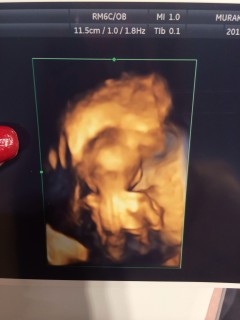

初腹エコーをやって3Dか4Dもとって貰いました。 リアルでびっくり!胎動が楽しみだな。

指しゃぶりかな!?

可愛くてずっとみていたかったです!

両手で目もとをおおっているところでした。右手のゆびが赤ちゃんらしくて、感激してしまいました。